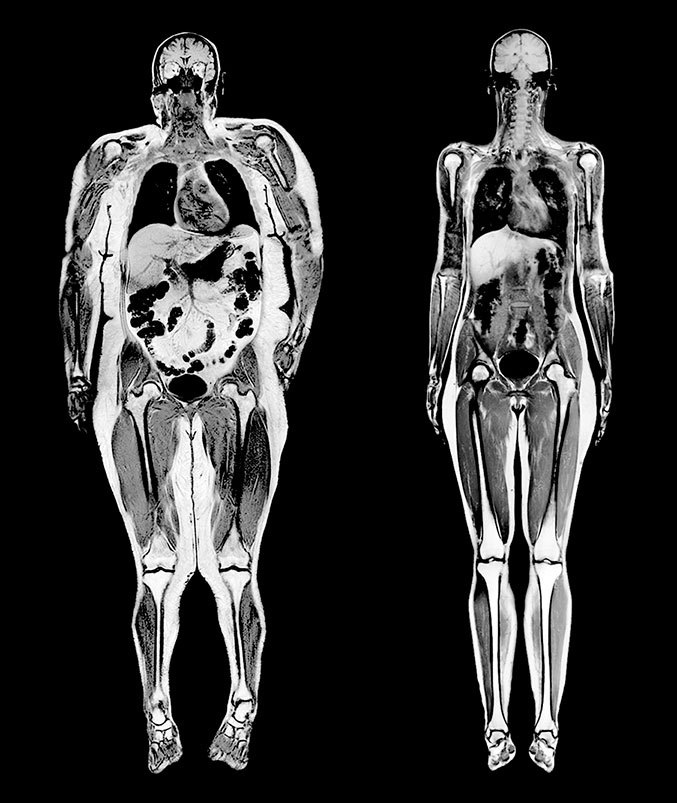

Думаете, жир скапливается только под кожей? Напрасно. На МРТ женщины весом в 114 кг, показанном в сравнении с МРТ женщины весом 54 кг, видны обширные отложения жира вокруг внутренних органов.